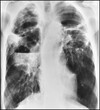

What pathology is seen here?

A

Cystic fibrosis

Lung looks scratchy